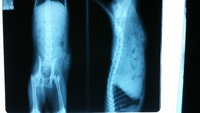

뒷다리를 전혀 못쓰기때문에 엑스레이 촬영 해봤더니

골절은 없지만 배쪽 탈장과 신경계쪽 문제인듯 하다고 (척추에도 손상이 있을꺼라고 하시더라구요)

몇일간 스테로이드 치료를 하기로 했습니다.